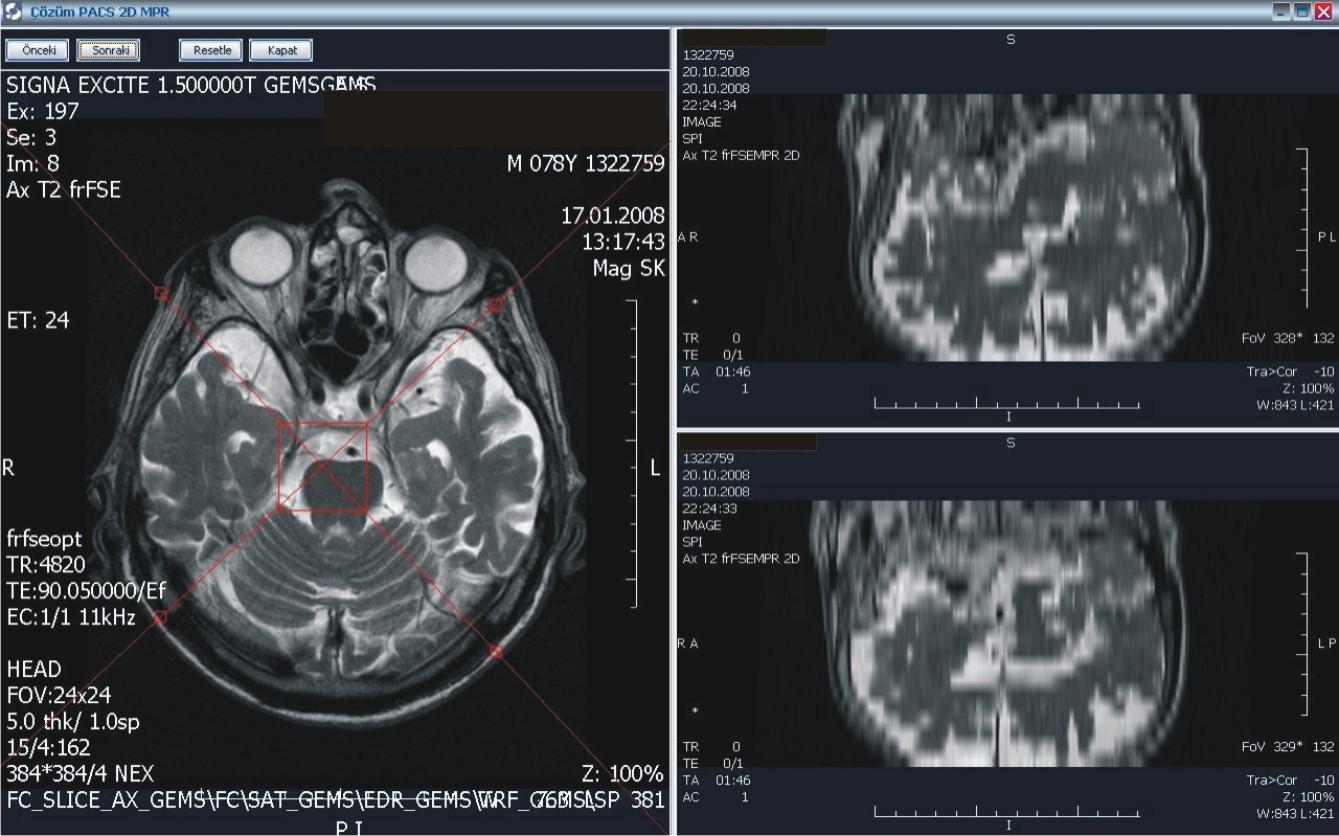

PACS ile, dijital olarak elde edilen panoramik ve lokal radyolojik görüntüler (ultrasonografi, doppler, magnetik rezonans, tomografi v.b. cihazlardan elde edilen veriler) çevrimiçi ortamlarda dijital arşivleme yöntemleriyle saklanıyor. Kayıpsız bir şekilde, hızlı ve güven içinde saklanan bu görüntüler, gerektiğinde istemcide yeniden görüntülenerek kullanılabiliyor.

Merkezi veri tabanında bilgilerin depolanması ile oluşan dijital arşiv (görüntüler üzerinde işlem yapmaya izin verecek şekilde yüksek çözünürlükte saklandığı için ölçüm ve tanıya ilişkin işlemler kolaylıkla yapılabiliyor), bilgilerin yeniden kullanılmasını arşivlenen bilgilerin modern tanı yöntemleri ile incelenmesini sağlıyor. Dijital görüntüler üzerinde işlem ve ölçüm yapılabiliyor. Görüntüler ve raporların her an, her yerde (tüm iş istasyonları üzerinden sorgulama yapılarak) ulaşılabilir olmasına ve görüntü işleme ve ölçüm (mesafe, açı, uzunluk, yoğunluk) yapılabilmesine imkan sağlıyor.

PACS, tanı ve teşhislerde daha doğru sonuçlar elde edilmesini sağlayarak  sonuçları  yorumlama ve raporlama süresini hızlandırıyor. Görüntülerin karşılaştırılması ve radyolojik bulguların geriye dönük değerlendirilmesi, karşılaştırmalı raporların incelenmesi, hekimin hastalığın gelişim sürecini daha iyi kavramasını ve doğru teşhisi daha hızlı bir şekilde koyabilmesini sağlıyor. Yedeklenen PACS görüntüleri istenildiğinde hastalara CD-DVD halinde veriliyor.